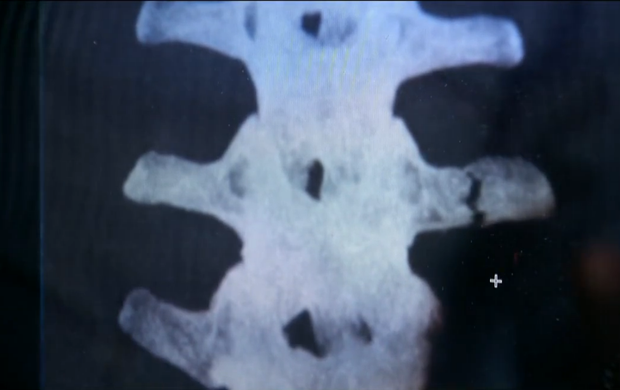

Um dos fatos marcantes da seleção brasileira na Copa do Mundo, a lesão de Neymar obrigou o então coordenador médico da equipe, José Luiz Runco, a ter de lidar com especulações sobre um possível retorno do atacante ao torneio, negado por ele desde o início por conta da gravidade do choque com o colombiano Zúñiga, nas quartas de final. Em entrevista ao “SporTV”, ele ressaltou a seriedade da lesão e mostrou com exclusividade a tomografia computadorizada da fratura na terceira vértebra lombar do jogador, feita logo após o jogo, em Fortaleza, com autorização de Neymar.

O exame mostra o corte na vértebra e evidencia a fratura. Por pouco a lesão não afetou a medula, o que deixaria Neymar em uma situação delicada, com chance de perda de movimentos.

– Você poderia ter um processo de uma raiz inflamada, que chamamos de radiculite. Ou seja, ele ia sentir um choque na perna. Você pode ter a compressão da medula que pode levar a um quadro de paraplegia momentânea ou paraplegia definitiva. Um quadro extremamente complicado – analisou Runco.